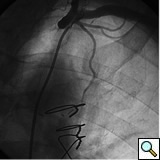

The most commonly used catheters for left heart catheterization and vein graft angiography can be seen in Figure 1 and Figure 4-13. Most of the vein grafts have horizontal take off and can be successfully engaged using a commonly used Judkins right number 4 (JR4) catheter. The JR4 catheter is the most commonly used catheter for the engagement of the right coronary ostium with horizontal take off. However, many vein grafts have unusual take off requiring different catheters. Many right coronary vein grafts have steep inferior take off making the ostial engagement with JR4 difficult or impossible (Figure 10). In such a scenario, a multipurpose catheter which has a shallow angulation is the best choice (Figure 11). The second major challenge in engaging vein graft ostia, particularly vein grafts supplying the left coronary arteries, is the shape of the aorta. A large aorta can make it very difficult for the JR4 catheter to reach the ostial vein grafts. In such a situation, Amplatz (AR) right and left (AL) catheters can be very helpful to reach the vein graft ostia. Amplatz catheters have a larger primary curve and have been used successfully in unusual superior take off of left coronary arteries or vein grafts and in large aorta. Amplatz catheters are available in different sizes (from smaller to larger curve: AR 1, AR2, AL2, AL2 and AL3). Occasionally, a very superior take off of a vein graft requires specially designed bypass graft catheters. Amplatz catheters are also extremely helpful in engaging native right coronary ostium with anterior take off.

PCI of the vein and arterial grafts have unique challenges. For any PCI, guide support is very important for successful balloon and stent delivery. In a tortuous vein graft with a steep angle, advancement of a stent can be very difficult and challenging. Therefore, it is important to choose the best available catheter before starting PCI. Similar to the right coronary angiography, a JR4 guide catheter is most commonly used in this setting. However, Amplatz guide catheters for left vein grafts and multipurpose catheters for right vein grafts are better choices in certain anatomy. In Figure 8 and Figure 10 two examples of poor guide support in two vein graft interventions can be seen. Initially, a JR4 guide was used for PCI of the vein graft supplying the left anterior descending artery (LAD) without any success. However, after changing the guide to an Amplatz left 2 guide catheter, we achieved excellent support without any difficulty in advancing two stents (Figure 9). In Figure 10, difficulty is illustrated in engaging the vein graft ostium supplying the right coronary artery with a JR4 catheter. This vein graft has a very steep inferior take off from the aorta. After changing the guide to a multipurpose catheter, we were able to deliver three stents successfully without any difficulties (Figure 11). Similar challenges exist in the treatment of the left IMA or right IMA. These arterial grafts can be extremely tortuous making stent delivery very difficult. It may be necessary to use short length stents for a better deliverability or stents with lowest profile. Usually, similar to the native coronary intervention, a 6 French guide is appropriate for the routine use.